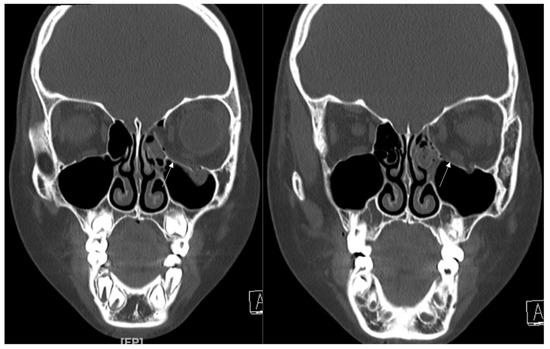

3.2. Case 2

A 48-year-old female patient came to our clinic with left eyeball swelling and ecchymosis caused by a car accident. The patient complained of pain and discomfort with eyeball movement (Figure 3). We surgically approached the medial orbital wall fracture seven days after the accident. After the subciliary incision, the fracture was exposed. The titanium-reinforced porous polyethylene (TR-PPE) plate was placed on the fracture site using a single screw at the inferior orbital rim (Figure 4). The patient was discharged on postoperative day 2 with significantly improved pain and discomfort.

Figure 3. Case 2. Preoperative facial CT scan (coronal view) of the 48-year-old female patient with left inferomedial orbital wall fracture. The titanium-reinforced porous polyethylene (TR-PPE) plate was placed on the inferomedial orbital wall using a single screw at the inferior orbital rim. (White arrow).

Figure 4. Case 2. Follow up facial CT finding (coronal view) of the same patient. The titanium-reinforced porous polyethylene (TR-PPE) plate was placed on the inferomedial orbital wall using a single screw at the inferior orbital rim. (White arrow).